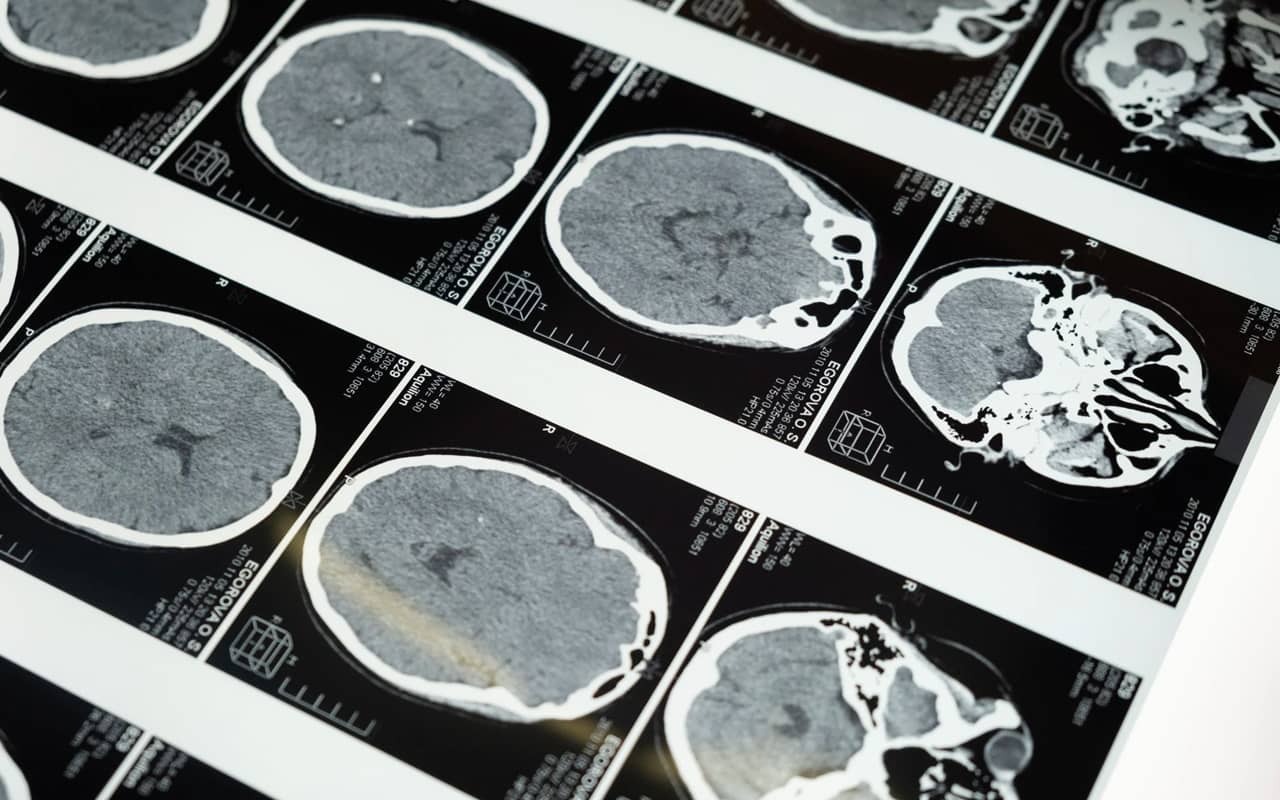

Second, we have tons of research demonstrating just how powerful practices like deity meditation are for enhancing the efficiency of your visuospatial processing. You’ll also want to check out the summaries of many scientific studies and brain scans in Andrew Newberg and Robert Waldman’s How Enlightenment Changes Your Brain.

Basically it says that visualizations are created in the prefrontal cortex, then the data is sent to the visual cortex. The combination of these two processes generate the visualization.

I suppose that I am able to create the image in the prefrontal cortex, but the info is not sent to the visual cortex or is sent, but is not processed correctly by the visual cortex

This supposition is based on the fact that I do get visual info, and not words, while trying to visualize, despite not not visualizing in the proper way.

I would caution you about creating suppositions about how your prefrontal cortex is or isn’t behaving, especially given the visual experience you’ve reported having in your dreams. From whence would your brain “get” visual info in this context?